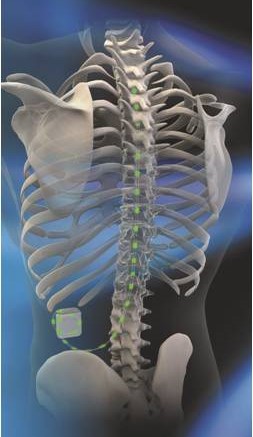

Η μέθοδος διέγερσης του νωτιαίου μυελού στηρίζεται στη μετάδοση ηλεκτρικών παλμών μέσω ηλεκτροδίων που τοποθετούνται  στον επισκληρίδιο χώρο της σπονδυλικής στήλης. Οι παλμοί αυτοί μεταδίδονται μέσω γεννήτριας, παρόμοιας ενός βηματοδότη, η οποία εμφυτεύεται υποδόρια στην κοιλιακή χώρα. Στόχο της διέγερσης του νωτιαίου μυελού αποτελούν οι νευρώνες που εμπλέκονται στην διαβίβαση και  στην επεξεργασία του πόνου. Η θεραπεία  ενεργοποιεί νευρωνικά κυκλώματα αναστολής του πόνου, προκαλώντας αντικατάσταση του αισθήματος πόνου  από ένα ήπιο αίσθημα καύσους ή νυγμού.

Με τον ασθενή σε πρηνή θέση και με ελαφρά καταστολή, τα επισκληρίδια ηλεκτρόδια που έχουν ήδη εμφυτευθεί συνδέονται κάτω από συνθήκες πλήρους αποστείρωσης με την γεννήτρια μέσω συνδετικού καλωδίου. Η γεννήτρια εμφυτεύεται υποδορίως στο πρόσθιο ή πλάγιο κοιλιακό τοίχωμα. Κατά τη διάρκεια της διαδικασίας, θα πρέπει να μπορεί ο  ασθενής να επιβεβαιώσει τη σωστή κάλυψη των επώδυνων περιοχών.